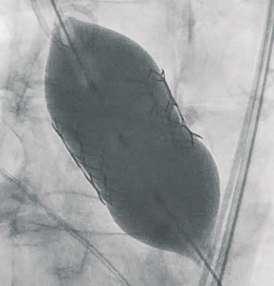

Navigator with Myval THVNavigator balloon with dual expansion ports at each end ensures rapid, simultaneous, controlled expansion (dog-boning) of distal and proximal ends

This typical dog bone pattern of inflation steadies the valve during expansion phase, ensuring its precise annular position and deployment without any risk of valve migration

Rapid balloon inflation, using an inflation device is possible with controlled palm thrust

Rapid balloon deflation within 3-5 sec ensures procedural safety and compliance